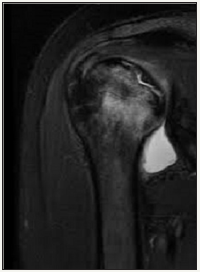

Figure 2:MRI view in case 1: the avascular necrosis of humeral head.

Radiographic evaluation: Standard radiological diagnoses include conventional x-ray images. True anterior-posterior (AP) view (Figure 1) showed subchondral sclerosis and a radiolucent area in humeral head. Also, there were some degenerative changes in the articular surface of humeral head. MRI determined the avascular necrosis of humeral head (Figure 2).